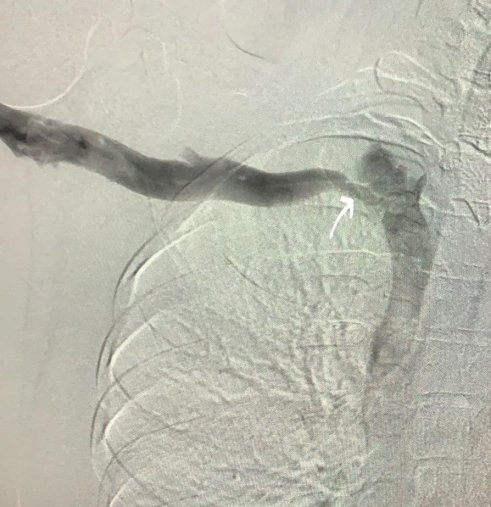

-Venografi: toplardamarlar değerlendirilir.

Resim: Torasik çıkış sendromunda ven basısı